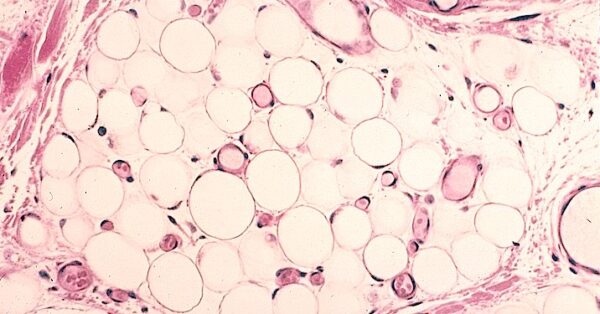

Conservar los lípidos neutros, como los que residen en las células adiposas, constituye un reto en el campo de la histología debido a la peculiaridad de estas moléculas, que son hidrofóbicas, es decir, repelen el agua. Para mantener la integridad de estos lípidos y permitir su observación en las muestras de tejido, es necesario emplear técnicas específicas. Una de estas técnicas es la realización de cortes por congelación en tejido previamente fijado en formalina, acompañada del uso de colorantes que se disuelven en grasas.

Los cortes por congelación implican la congelación rápida de las muestras de tejido previamente fijado. Este proceso preserva las estructuras lipídicas y evita la pérdida de lípidos durante el corte en secciones delgadas. Esto es especialmente crítico para los adipocitos, cuya función principal es almacenar grandes cantidades de lípidos.

Para visualizar los lípidos en las células adiposas en las secciones de tejido, se recurre a colorantes que son liposolubles, es decir, que se disuelven en grasas. El colorante más comúnmente utilizado para este propósito es el «aceite rojo O,» que se une a los lípidos y les otorga un color rojo o anaranjado cuando se observan bajo el microscopio. También existen otros colorantes liposolubles que pueden ser empleados para fines similares.